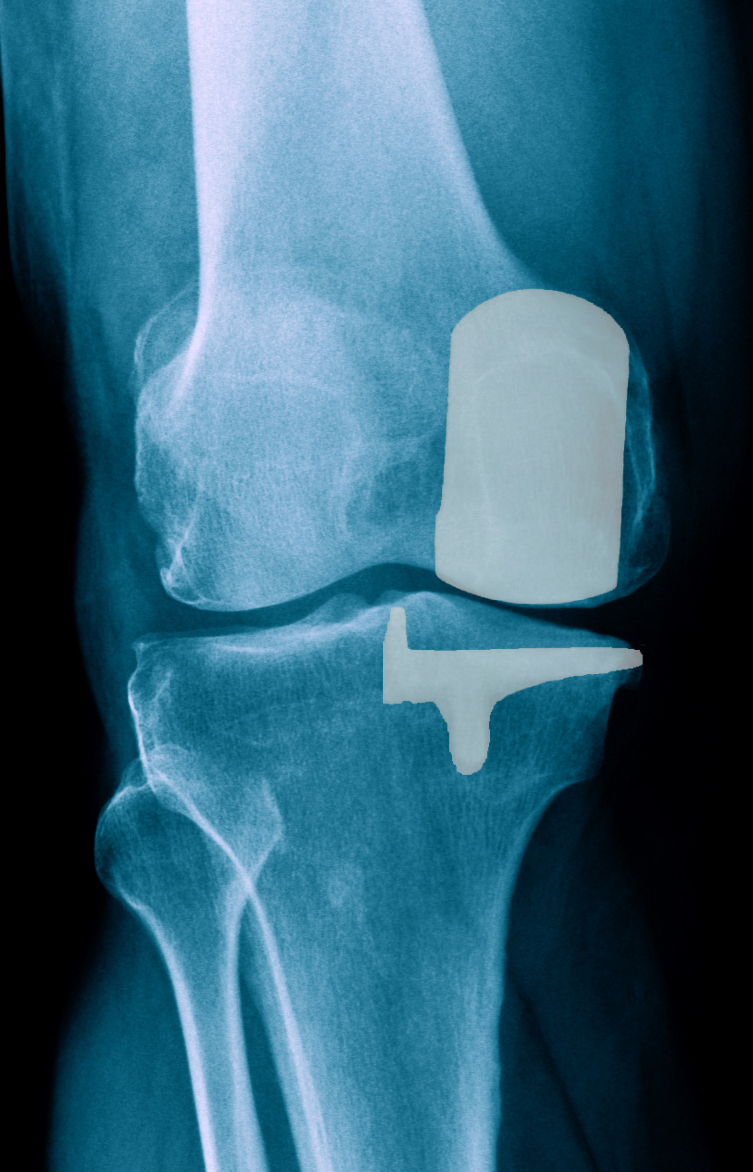

Первичное одномыщелковое эндопротеизрование коленного сустава

Первичное одномыщелковое эндопротеизрование коленного сустава. В случае поражения только одного мыщелка колена (латерального или медиального) при сохранности связочного аппарата применяется одномыщелковое протезирование коленного сустава.